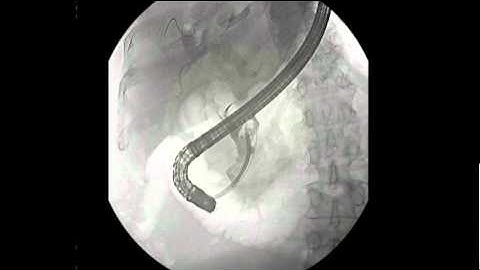

ERCP + SPYGLASS CHOLANGIOSCOPY GUIDED HOLMIUM LASER LITHOTRIPSY FOR LARGE CBD STONE